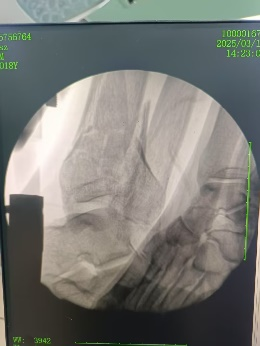

安裝外固定架

六軸機器人輔助下腓骨穿針